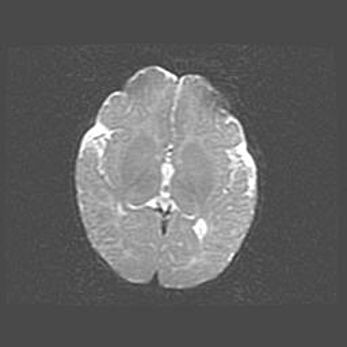

Церебральная ишемия II.

Возраст: 5 дней

Вес: 3400 г

Пол: женский

Окружность головы: 35 см

Срок гестации: 39 недель

Церебральная ишемия – это заболевание, характеризующееся недостаточностью (гипоксией) либо полным прекращением (аноксией) снабжения мозга кислородом по причине закупорки одного или нескольких сосудов. Это приводит к  что метаболическим расстройствам различной степени тяжести в тканях головного мозга, развитию коагуляционных некрозов и гибели нейронов.